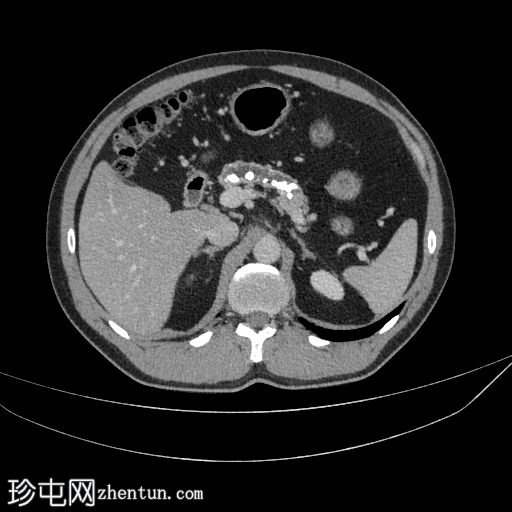

轴位

轴位增强扫描(门静脉期)

胰腺萎缩、粗大钙化及主胰管扩张

无急性胰腺炎征象

肝脂肪变性

左侧结肠憩室

主胰管扩张、胰腺萎缩和钙化是慢性胰腺炎诊断的关键。该患者有反复发作的急性胰腺炎病史。